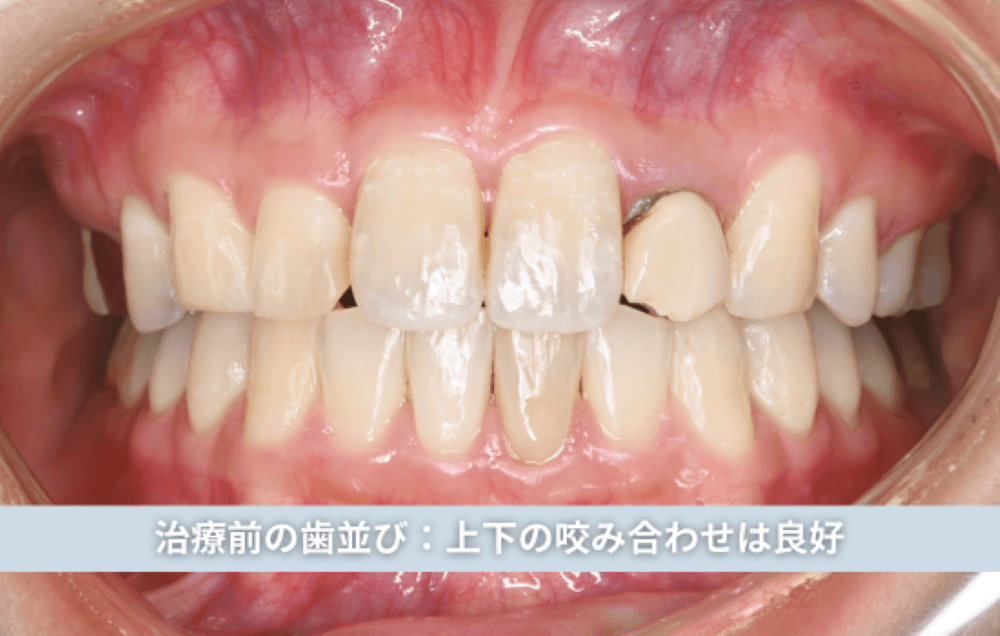

初診時、歯並び自体は整っており、上下の歯の噛み合わせも安定していました。しかし横顔や笑顔の印象を詳しく確認すると、前歯の位置と傾斜が顔貌のバランスに対して後方に位置している状態が認められました。

治療前の状態

すでに矯正治療を終えられていたため、歯列に大きなガタつきはなく、上下の歯の咬み合わせも良好でした。